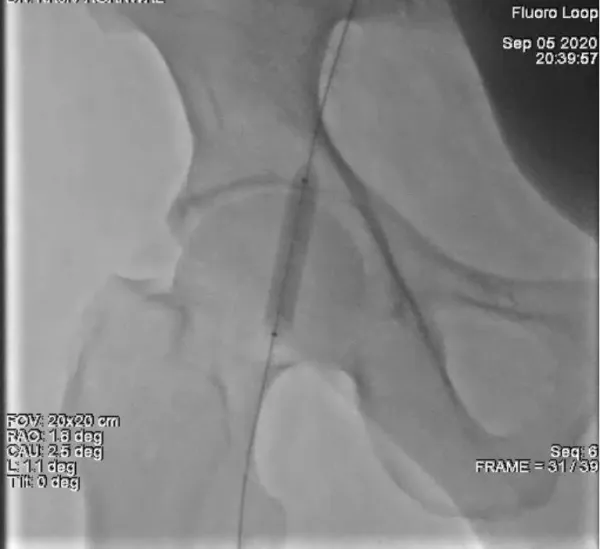

Through the Judkins right (JR) 6 catheter, a 0.035 inch magic torque guide wire (260 cm) [Boston Scientific] was passed across the common femoral artery into the distal right superficial femoral artery. The JR6 catheter was then withdrawn leaving the wire in the distal superficial femoral artery. A 8 x 40 Armada 35 PTA Balloon (Abbott Vascular) was inserted over the magic torque guide wire and balloon tamponade was performed over the leaking site for a total of 15 min at a inflation pressure of 4 atm (Figure 3). Total two inflations were done with a gap of 5 minute in between.

Figure 3: Demonstrates Balloon tamponade of the leaking right common femoral artery via left femoral approach.